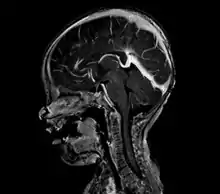

vein of Galen malformation

A cerebral AVM diagnosis is established by neuroimaging studies after a complete neurological and physical examination.[5][12] Three main techniques are used to visualize the brain and search for an AVM: computed tomography (CT), magnetic resonance imaging (MRI), and cerebral angiography.[12] A CT scan of the head is usually performed first when the subject is symptomatic. It can suggest the approximate site of the bleed.[3] MRI is more sensitive than CT in the diagnosis, and provides better information about the exact location of the malformation.[12] More detailed pictures of the tangle of blood vessels that compose an AVM can be obtained by using radioactive agents injected into the blood stream. If a CT is used in conjunction with an angiogram, this is called a computerized tomography angiogram; while, if MRI is used it is called magnetic resonance angiogram.[3][12] The best images of a cerebral AVM are obtained through cerebral angiography. This procedure involves using a catheter, threaded through an artery up to the head, to deliver a contrast agent into the AVM. As the contrast agent flows through the AVM structure, a sequence of X-ray images are obtained.[12]